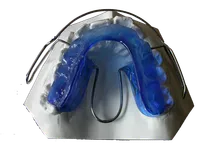

Mandibular Advancement Device (MAD)

Dispositivo ortodontico personalizzato per il trattamento delle apnee del sonno (OSAS) e del russamento cronico. Mantiene la mandibola in posizione avanzata durante il sonno, migliorando significativamente il flusso respiratorio e la qualità del sonno.